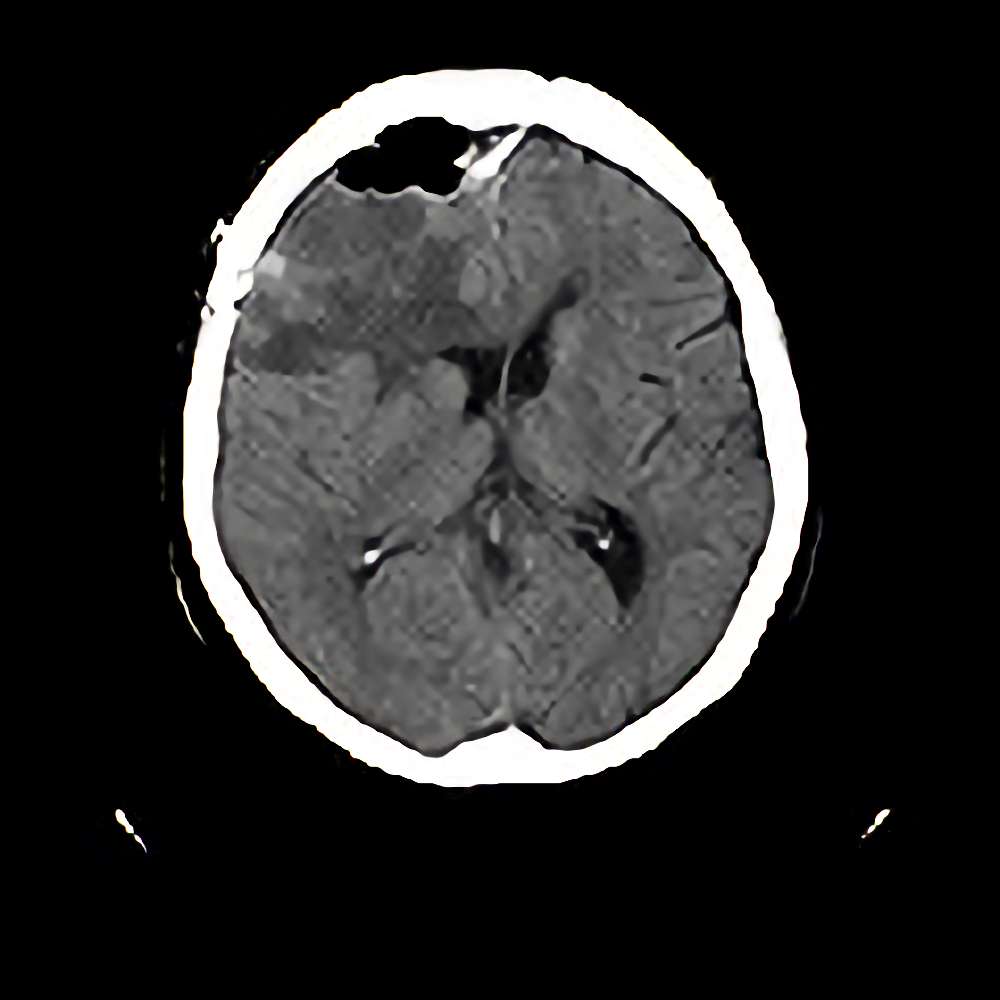

脳腫瘍 手術実績

症例 '12年10月

No.

※ 画像をクリックすると拡大表示します。症例No.は平成29年から起算しています。

年_番号

手術年月

患者年齢

’12_179

'12年10月

70代

病名

術式

備考

悪性髄膜腫

断層撮影

手術前

1

手術前2

手術後